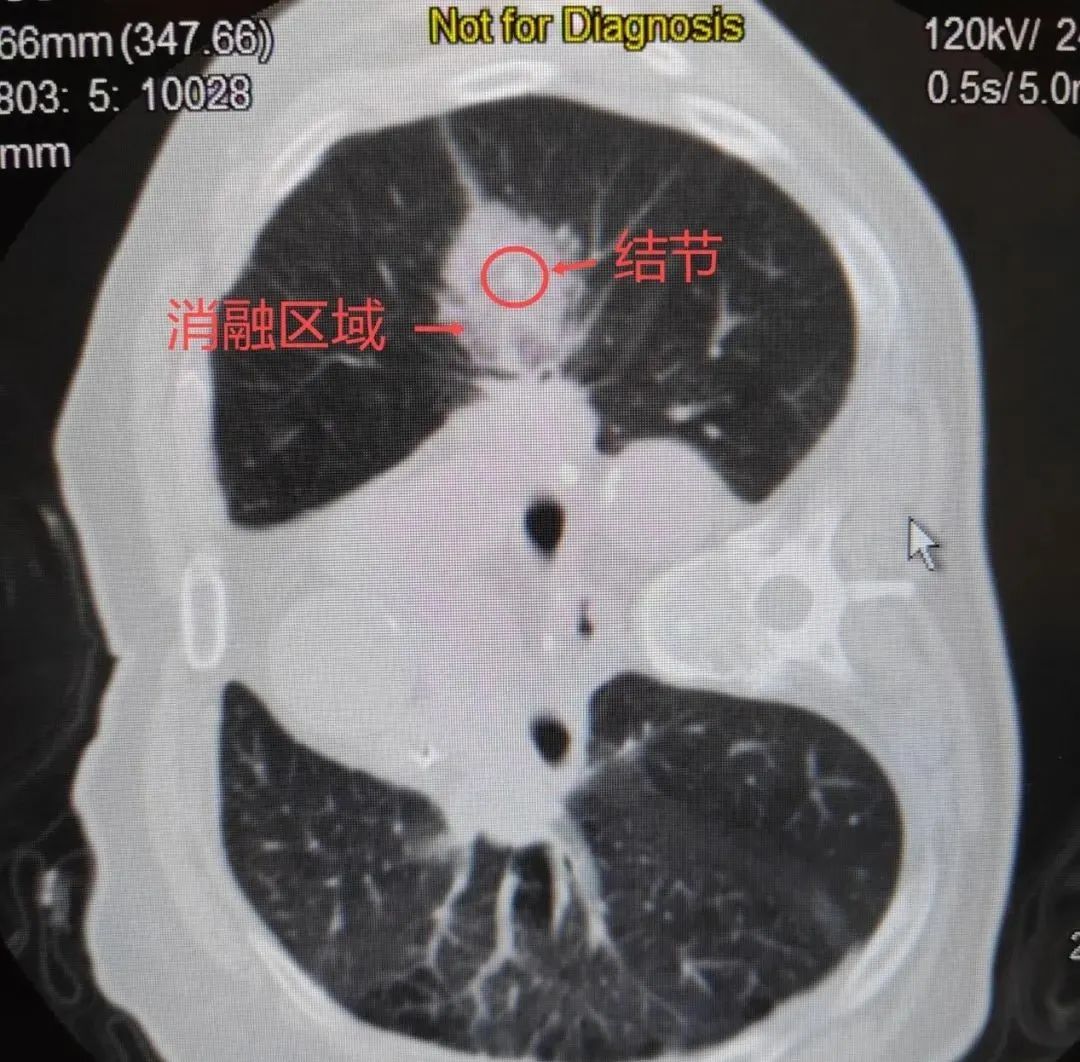

在国内率先开展冷热复合式消融技术

为肺部肿瘤的治疗

冷热复合式消融技术的独特之处首先体现在它以外科技术为核心,巧妙地融合了冷热复合式消融理念。在治疗过程中,科室依托先进的多学科协作诊疗(MDT)模式,组织多领域专家对患者的肿瘤特征、全身状况以及治疗耐受性进行全面而细致的综合评估。这种精准的评估体系能够根据患者的具体情况,在微创腔镜手术、介入消融等多种治疗策略中,为患者量身定制个体化的治疗方案。